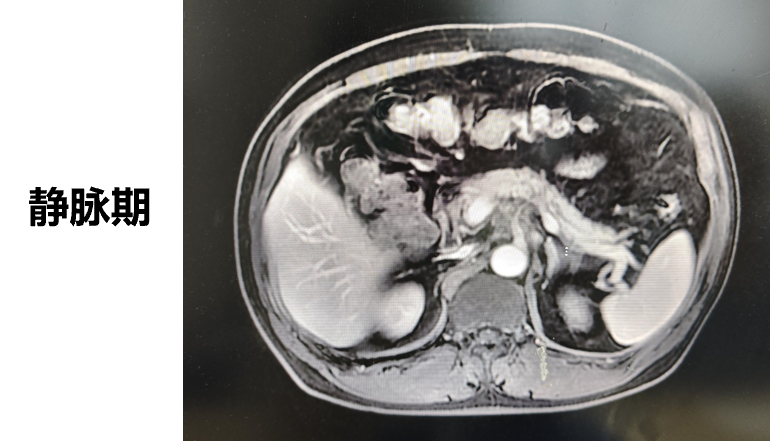

◈ 2023-3-9 上腹部MR增强扫描,对比2023-1-19上腹部MR:胰周多发囊性病变,考虑为术后改变(活检后),假性囊肿形成可能,较前吸收缩小;肠系膜上动脉、腹腔干近段及局部分支周围软组织影,较前缩小,研究者评估整体疗效为部分缓解(PR)。

2023-3-9上腹部MR增强扫描—TTFields联合化疗治疗五月余